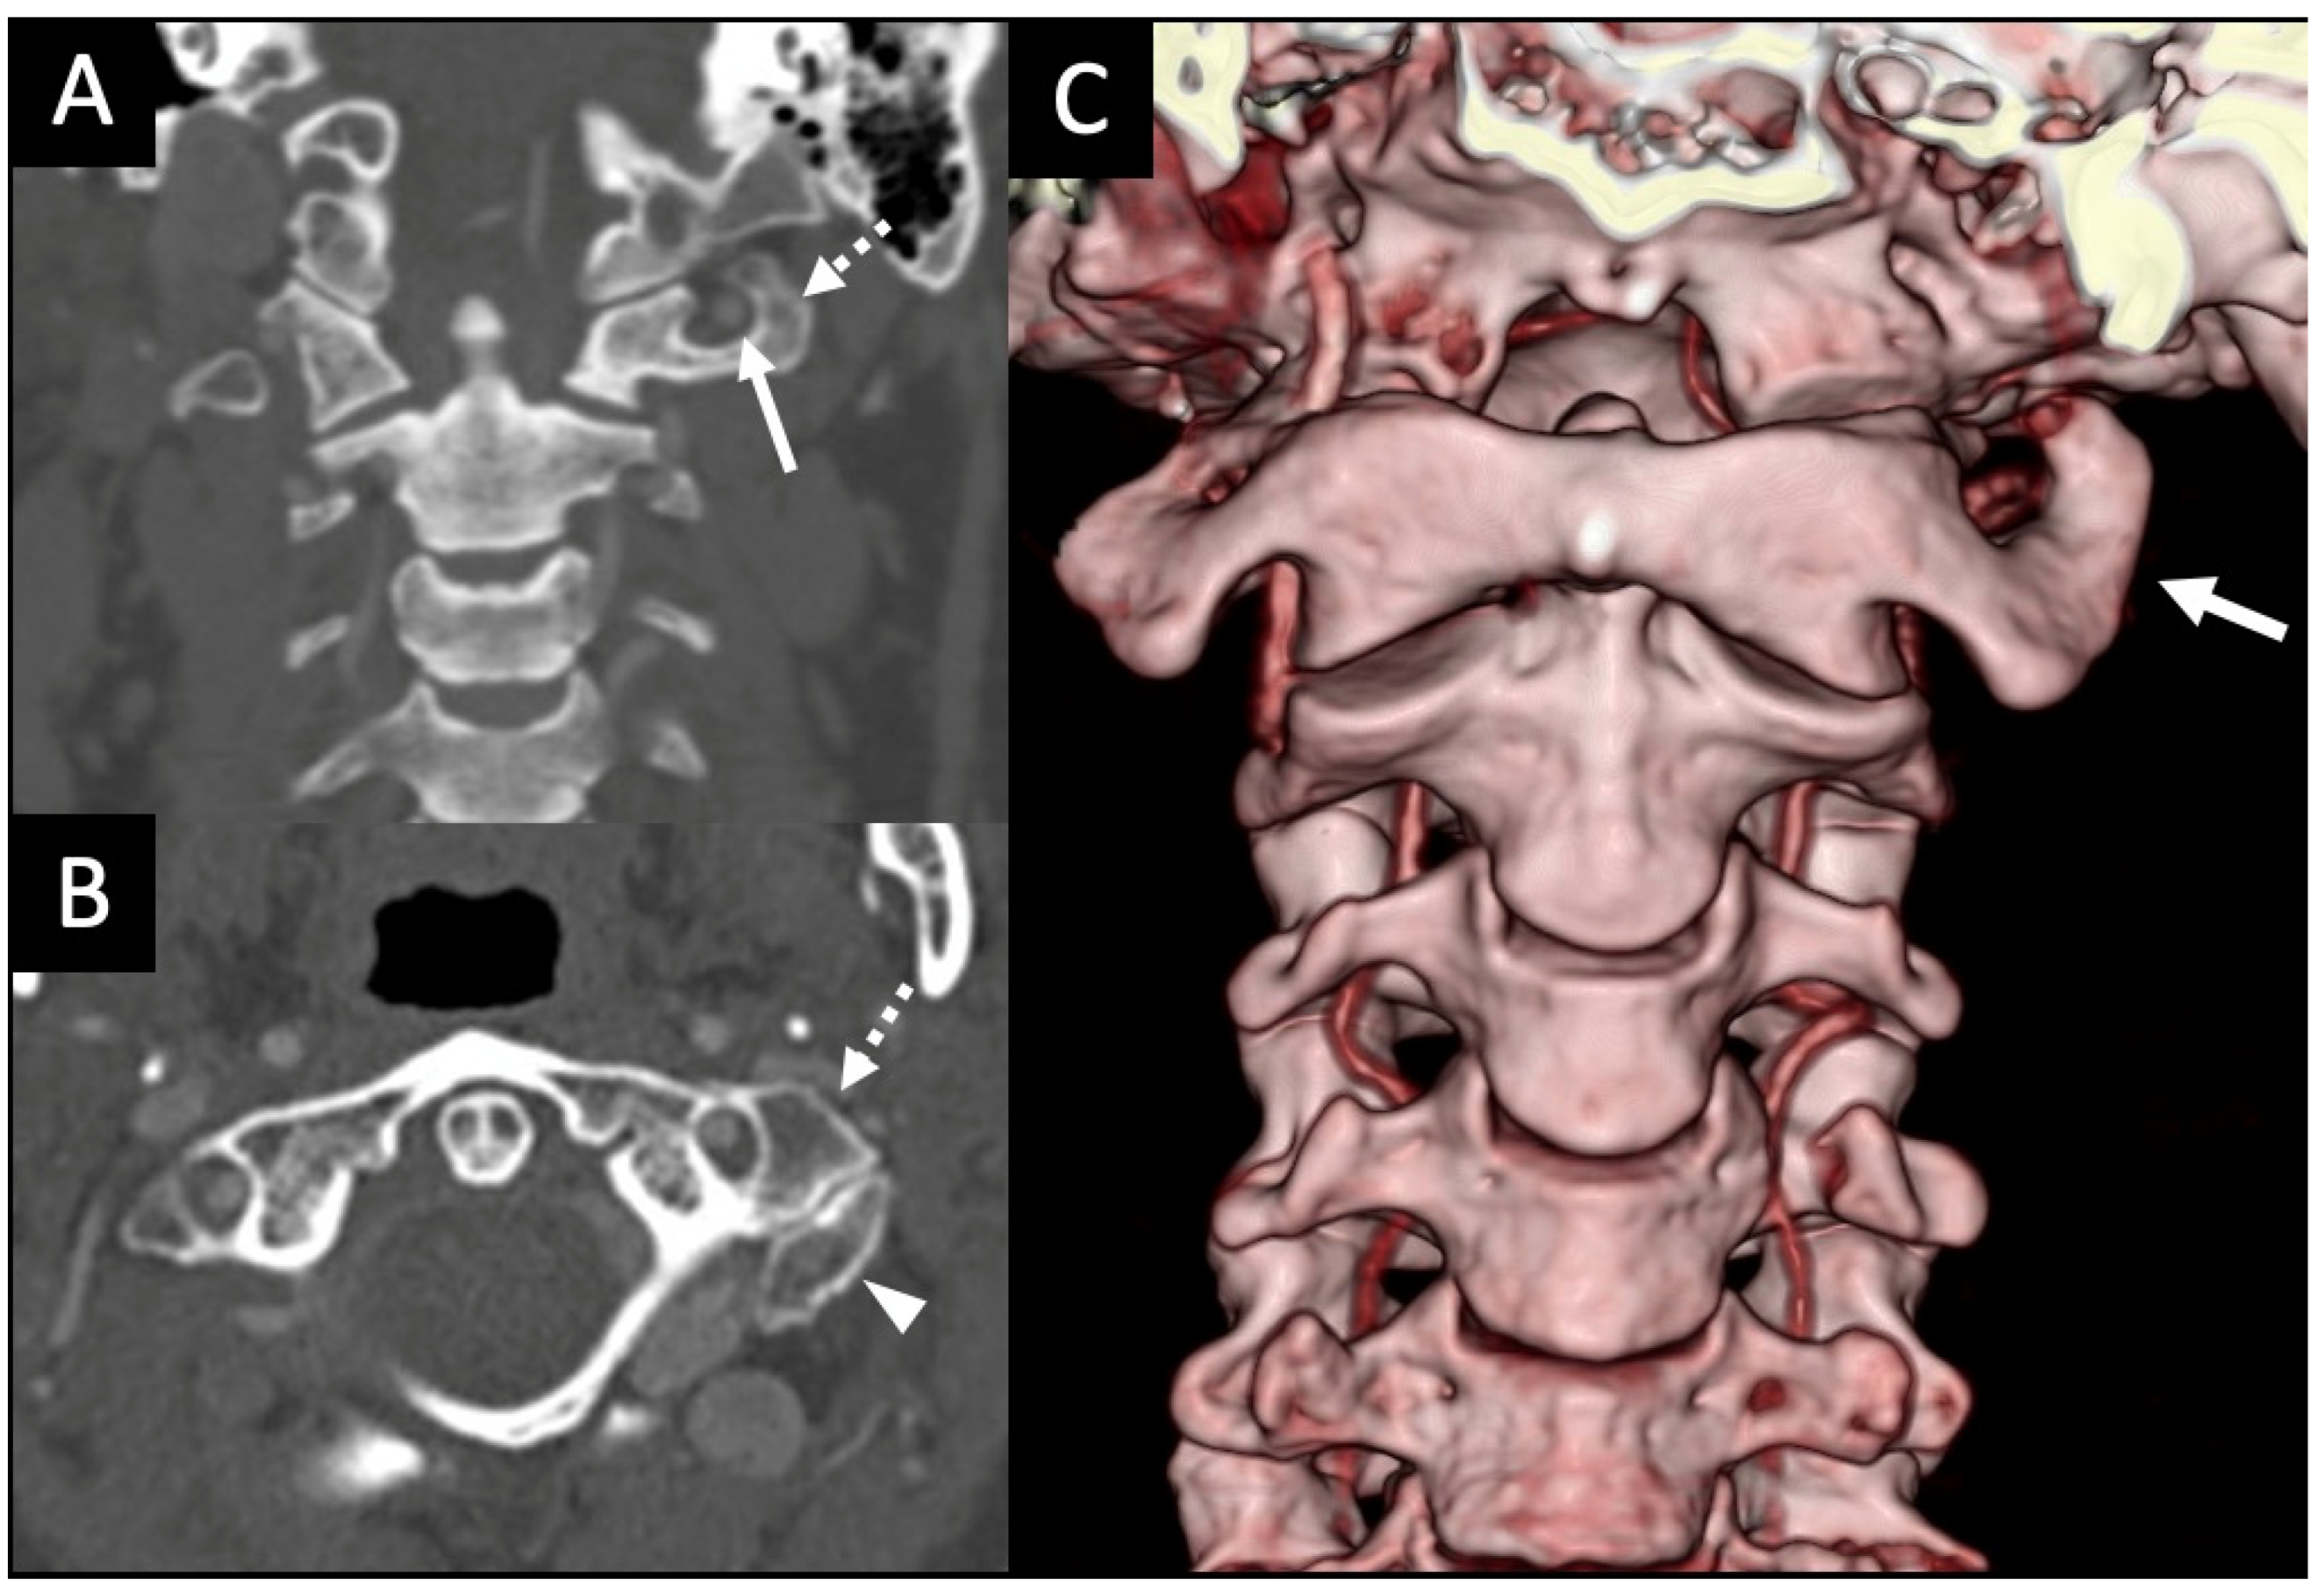

3.2. Variations of the V3 Segment